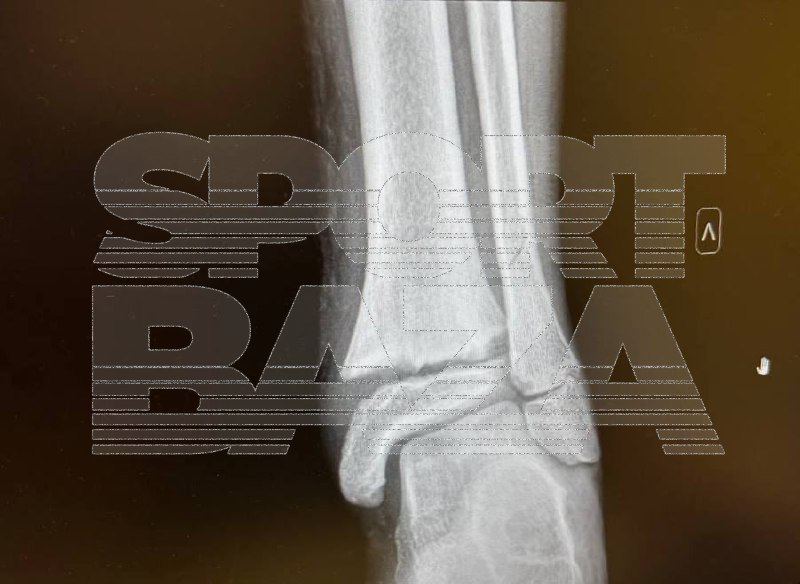

В больнице у мальчика диагностировали переломы малой и большой берцовых костей со смещением.